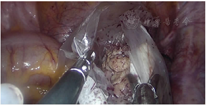

诊治经过:综合病史、体格检查及辅助检查。术前诊断:子宫肌瘤、宫内膜息肉待诊;遂于2020年2月24日行宫腔镜检查及TU-LESS子宫肌瘤挖除术。宫腔镜术中见:两侧宫角及子宫后壁均可见息肉样突起,直径约1 cm,术中冰冻病理结果提示子宫内膜呈增生期组织像。腹腔镜下见子宫增大如孕2个月大小,后壁肌壁间突向浆膜下可见一直径约5 cm×5 cm×6 cm的肌瘤样突起,实性、质软,切面呈灰黄色、未见明显旋涡状结构,与子宫肌壁界限欠清,考虑恶性不能排除,术中及时将标本袋置于瘤体周围继续挖除,以减少病灶在盆腹腔内的播散(图2)。全部标本装袋后于脐部切口经冷刀旋切取出(图3)。术中冰冻病理结果显示高度怀疑子宫内膜间质肉瘤(endometrial stromal sarcoma,ESS)(低级别),待冻后石蜡病理结果确定。术中与患者家属沟通,鉴于患者年轻,且术中冰冻病理与术后石蜡病理结果可能存在不一致,选择暂不扩大手术范围,等待术后石蜡病理结果。